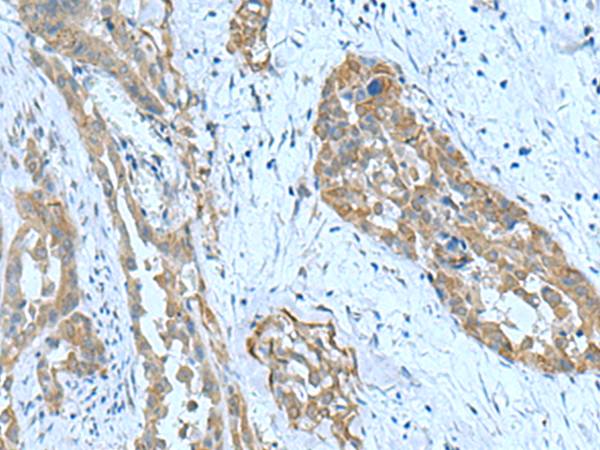

分类: 科研抗体货号: P10203别名: RaLP; SHCD应用: IHC反应种属: Human